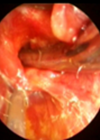

Recurrent respiratory papilloma treatment in the office

In this interesting new article, Markus Hess and Susanne Fleischer describe their technique for managing recurrent laryngeal papillomatosis in an outpatient setting using channelled endoscopes. The recurrent respiratory papillomatosis (RRP) of the larynx is a chronic HPV-associated viral disease. Clinical...